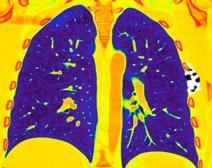

Derrame pleural..33,3% Derrame bilateral.26,7% Ganglios mediastínicos e hiliares..66,7%..

No hiliares

Okada F et al. Chest HRCT findings in acute transformation of adult T-cell lymphoma/leukemia. Eur Radiol 2015

Vidrio deslustrado 60%. Consolidación 33,3% Nódulos…33,3%